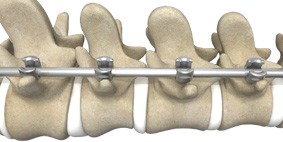

When reaching this step in the operating room, your surgeon positions the Mako Robotic-Arm over the surgical site. Mako Spine is designed to align to your personalized surgical plan. Once aligned, Mako Spine holds a guide tube in place, allowing your surgeon to “prepare the bone” or use instruments to make holes through the bones that connect the back of the vertebrae to the vertebral bodies in the front of the spine. These connecting bones are called pedicles, and the specialized implantable screws placed into them are called pedicle screws. Once the bone is prepared, Mako Spine helps your surgeon place the pedicle screws as planned.

Spine surgery generally involves several steps that may include accessing the affected area of the spine, removing diseased or damaged bone and/or disc material, placing implants, and securing the spinal bones with specialized implantable screws – a process referred to as fixation. Fixation refers to the surgical stabilization of the vertebrae (spinal bones) using specialized implants called screws and rods.